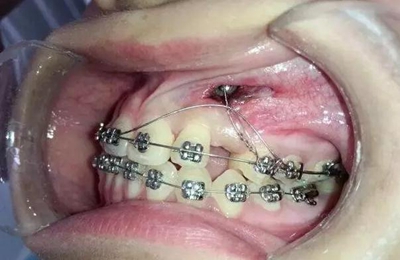

幾天過后病人向我反應(yīng)側(cè)切牙壓痛松動(dòng)

我考慮一下應(yīng)該是尖牙牙冠壓迫壓迫側(cè)切牙的根尖部導(dǎo)致的疼痛和松動(dòng)

考慮到如果能像種植支抗,水平方向或者向唇側(cè)牽引移動(dòng),可以有效避免垂直方向牽引力壓迫側(cè)切牙根尖部,所以我和病人溝通了一下,建議采用種植支抗,但是病人不想增加費(fèi)用。

那好吧還是采用輔弓增加支抗,經(jīng)濟(jì)適用,也便與操作,0.8不銹鋼絲彎制,進(jìn)行熱處理,增加其彈力。

結(jié)扎固定